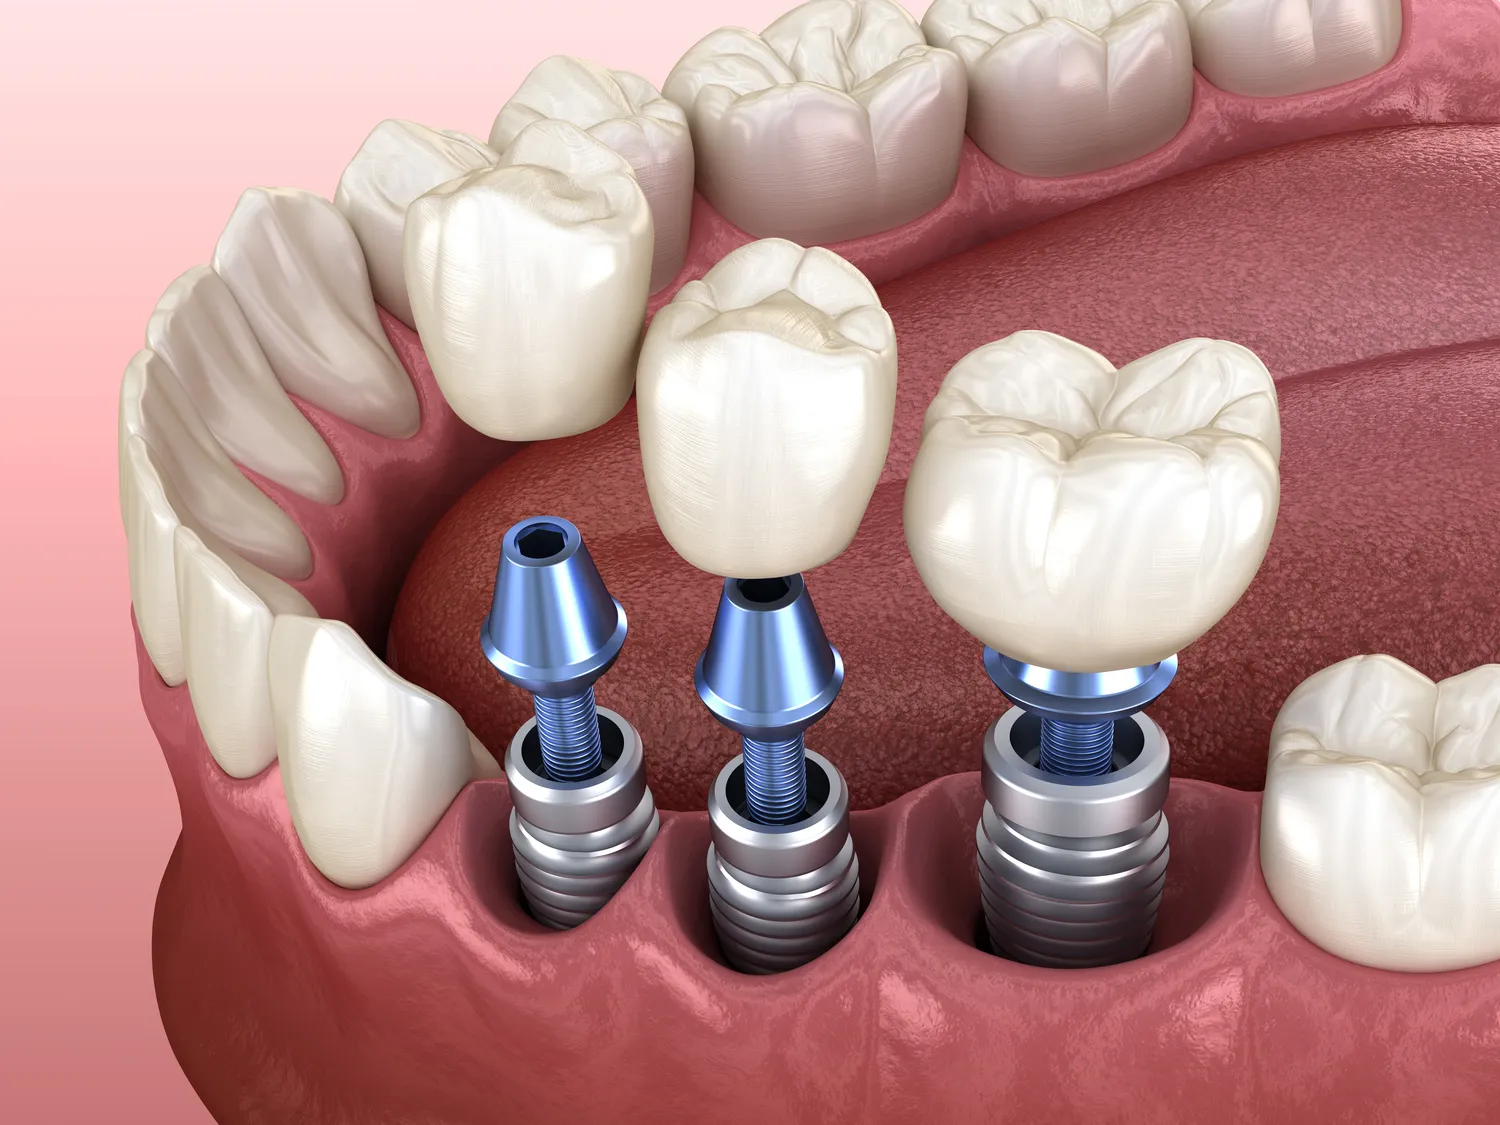

W ostatnich latach rozwój technologii w dziedzinie implantologii zębów znacząco wpłynął na jakość i bezpieczeństwo zabiegów. Nowoczesne metody, takie jak cyfrowe planowanie leczenia, pozwalają na precyzyjne zaplanowanie każdego etapu wszczepienia implantu. Dzięki zastosowaniu tomografii komputerowej możliwe jest uzyskanie trójwymiarowego obrazu kości, co umożliwia dokładne określenie miejsca wszczepienia implantu oraz ocenę jego stabilności. Wprowadzenie technologii CAD/CAM do produkcji koron i mostów protetycznych pozwala na szybsze i bardziej precyzyjne wykonanie uzupełnień protetycznych. Dodatkowo, techniki takie jak implanty natychmiastowe, które można wszczepić w tym samym dniu co ekstrakcja zęba, stają się coraz bardziej popularne. Dzięki temu pacjenci mogą cieszyć się nowym uśmiechem w krótszym czasie. Warto również wspomnieć o zastosowaniu materiałów biokompatybilnych, które minimalizują ryzyko odrzutu implantu przez organizm.